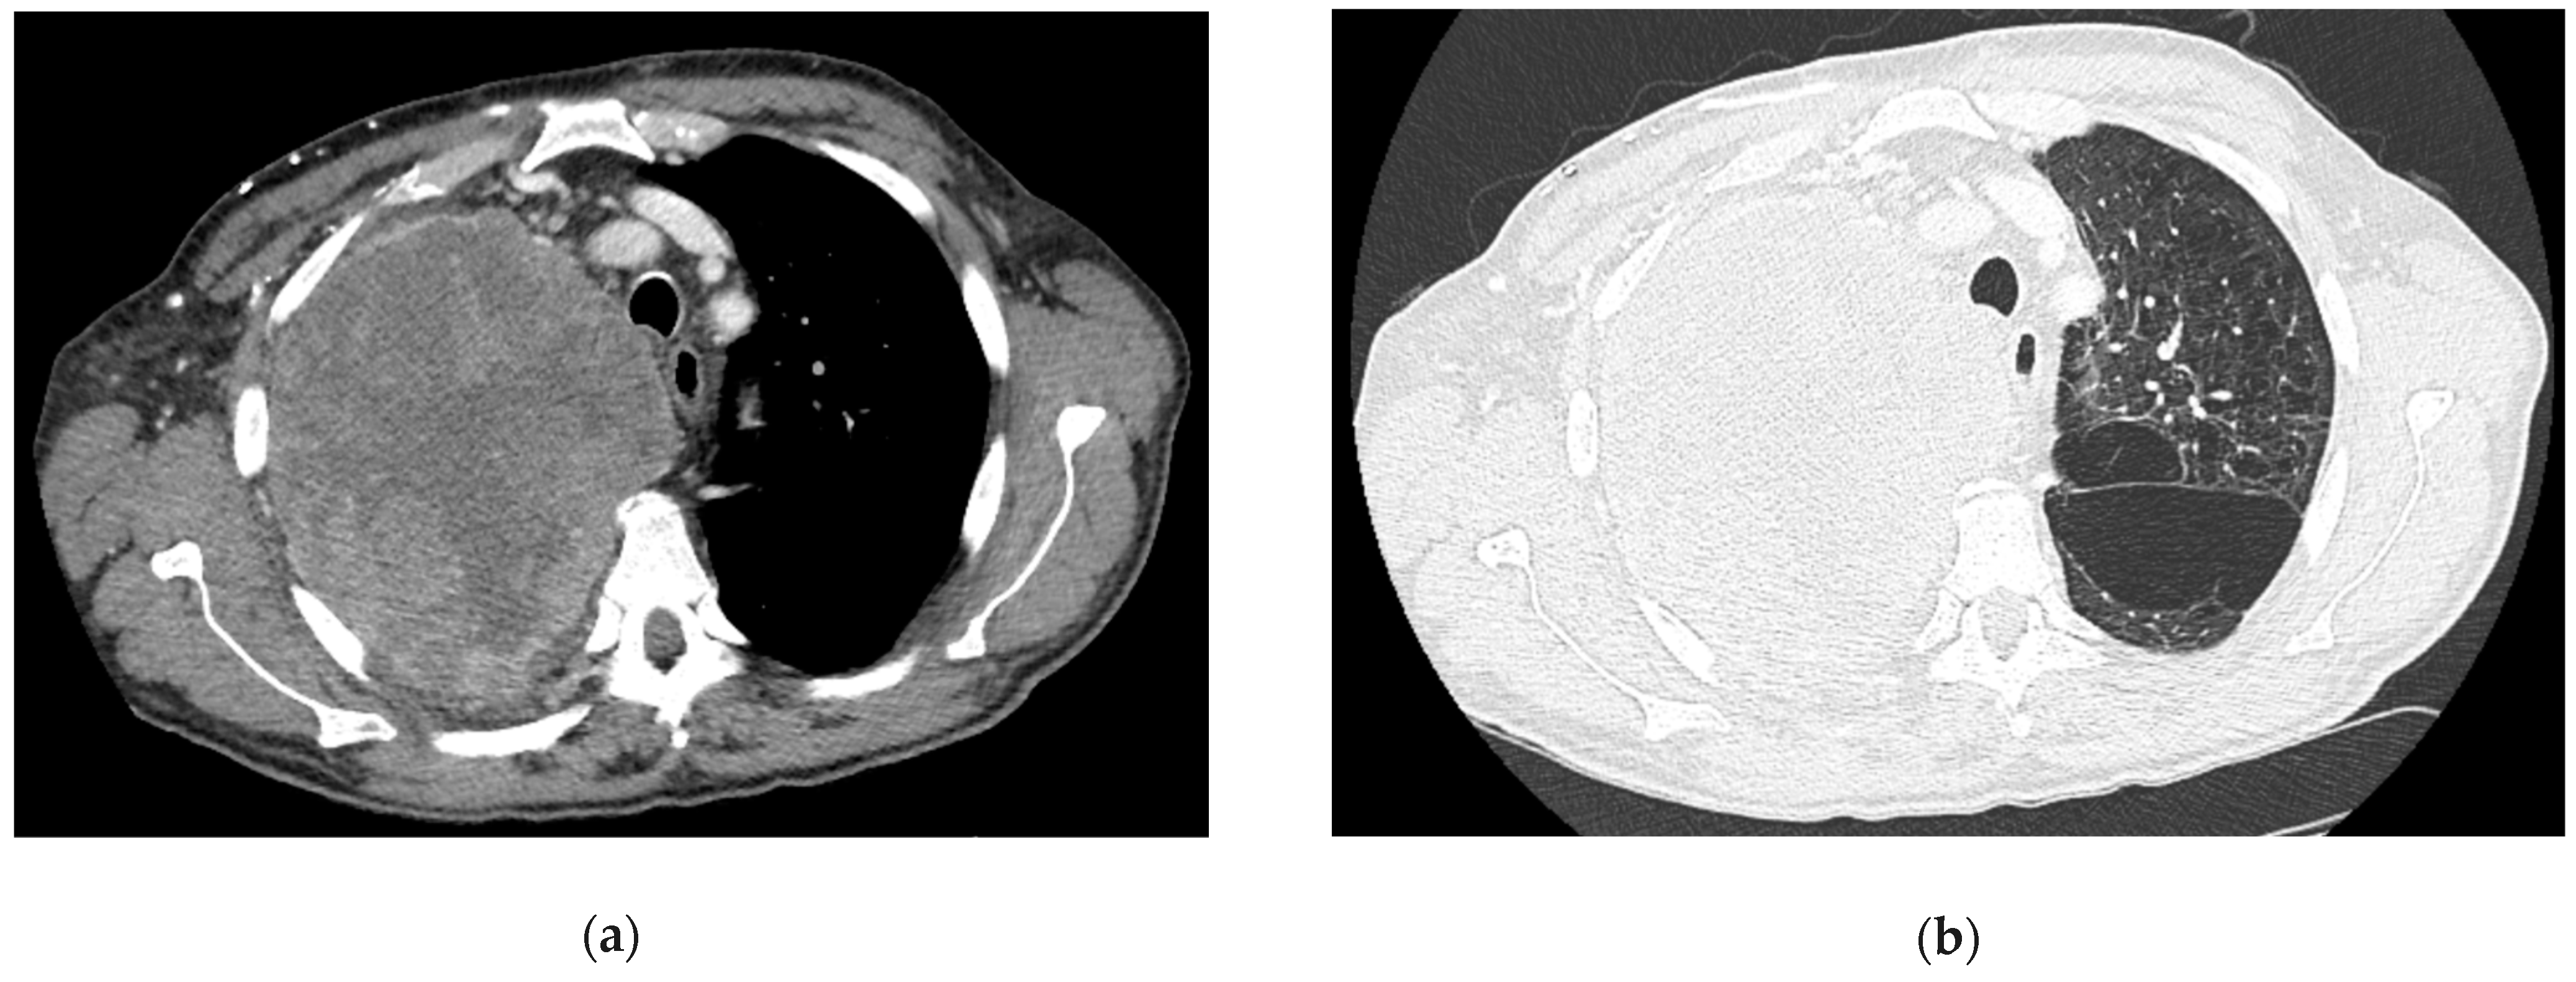

5.3. Computed Tomography (CT)

5.4. Magnetic Resonance Imaging (MRI)

6.7. Image-Guided Percutaneous Transthoracic Needle Biopsy (PTNB)